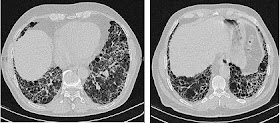

| Fibrose Pulmonaire Idiopathique.Tomodensitométrie haute résolution des poumons d'un patient atteint de Fibrose Pulmonaire Idiopathique. (...) Source iconographique et légendaire: https://fr.wikipedia.org/wiki/Fibrose_pulmonaire_idiopathique |